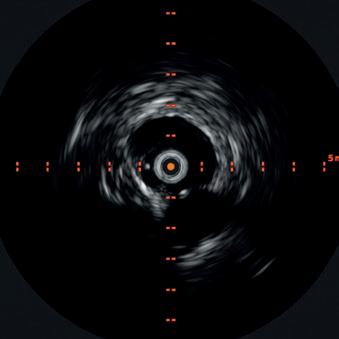

An arteriogram of the left lower extremity was performed via antegrade left common femoral artery access based on preoperative review of the lower extremity arteriogram from Uzbekistan. Scattered non-calcified plaque with moderate to high-grade stenoses were identified in the proximal and mid superficial femoral artery. Diffuse severe calcified tibial artery disease was identified. There was a long segment stenosis of the proximal and mid posterior tibial artery coupled with a more distal occlusion. The proximal peroneal artery was calcified and occluded with distal reconstitution identified. There was complete occlusion of the anterior tibial artery (Figure 2).

Shockwave E8 3mm x 80mm to the posterior tibial artery

The posterior tibial artery was successfully crossed first. The long-length posterior tibial artery disease was treated with a Shockwave E8 3.0mm x 80mm IVL catheter, with no pre-dilatation required. A total of 200 pulses were delivered along the length of the posterior tibial artery (Figure 3).

Shockwave E8 3mm x 80mm to the peroneal artery

Following this, the peroneal artery occlusion was successfully crossed. The longlength peroneal artery disease was treated with the same Shockwave E8 3mm x 80mm IVL catheter also with no pre-dilatation required. The remaining 200 pulses were

delivered across the length of the peroneal artery disease (Figure 3).